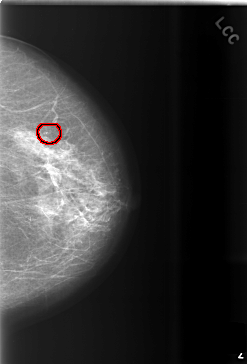

C_0508_1.LEFT_CC

FILE: C_0508_1.LEFT_CC.OVERLAY

TOTAL_ABNORMALITIES 1

ABNORMALITY 1

LESION_TYPE CALCIFICATION TYPE PUNCTATE DISTRIBUTION CLUSTERED

ASSESSMENT 3

SUBTLETY 4

PATHOLOGY BENIGN

TOTAL_OUTLINES 1

BOUNDARY